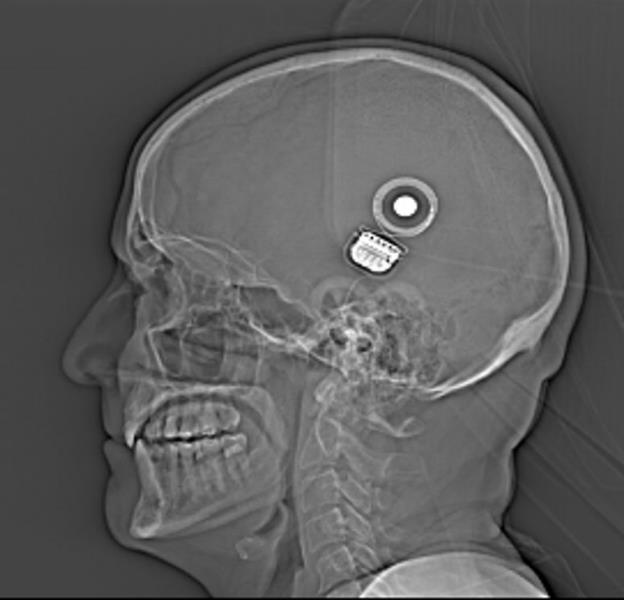

Here’s the CT scan showing the implant on the side of my head. The smaller, very white round spot is the magnet, to which the external coil is attracted.